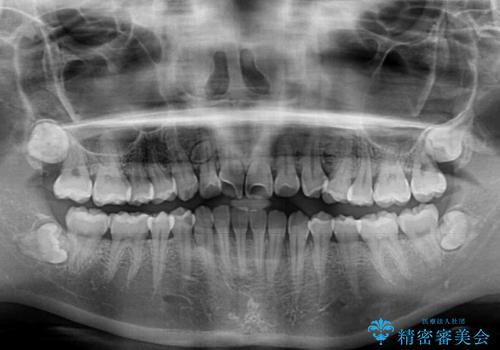

- 上顎歯列と下顎前歯の叢生を気にして来院された患者様です。

上顎からワイヤー矯正を開始し、終了間際から下顎前歯の叢生解消するよう計画しました。

部分矯正でしたが、咬み合わせに違和感が出ることなく気になる部分を改善させることができました。